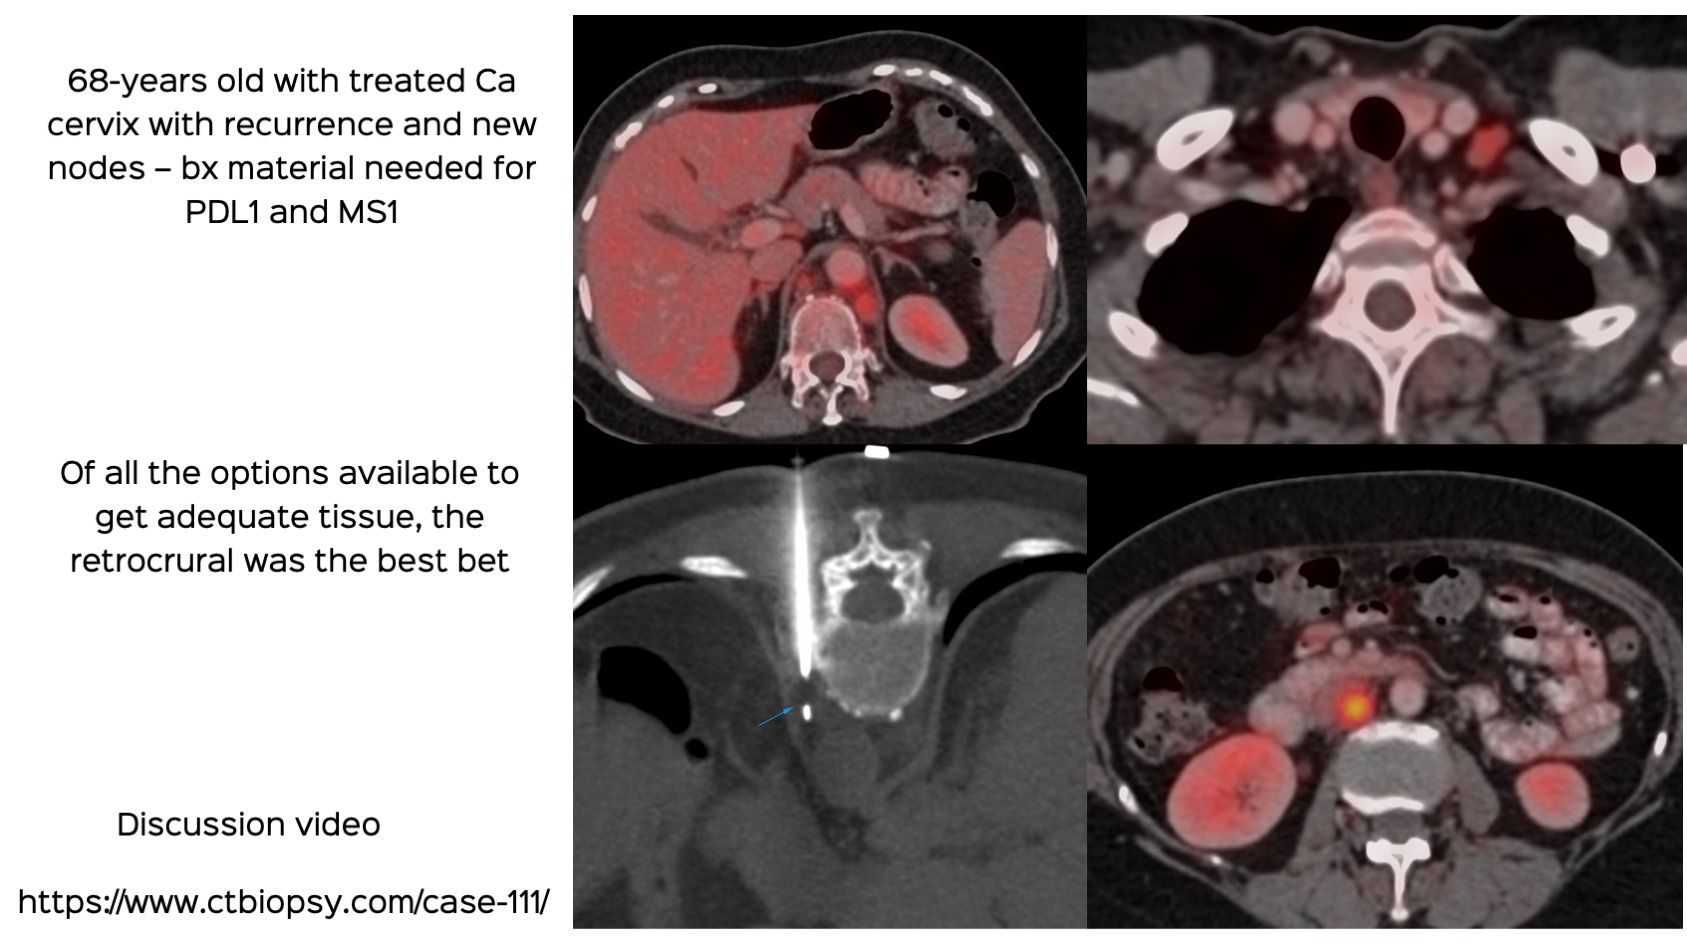

Case 111: Retrocrural Node Biopsy